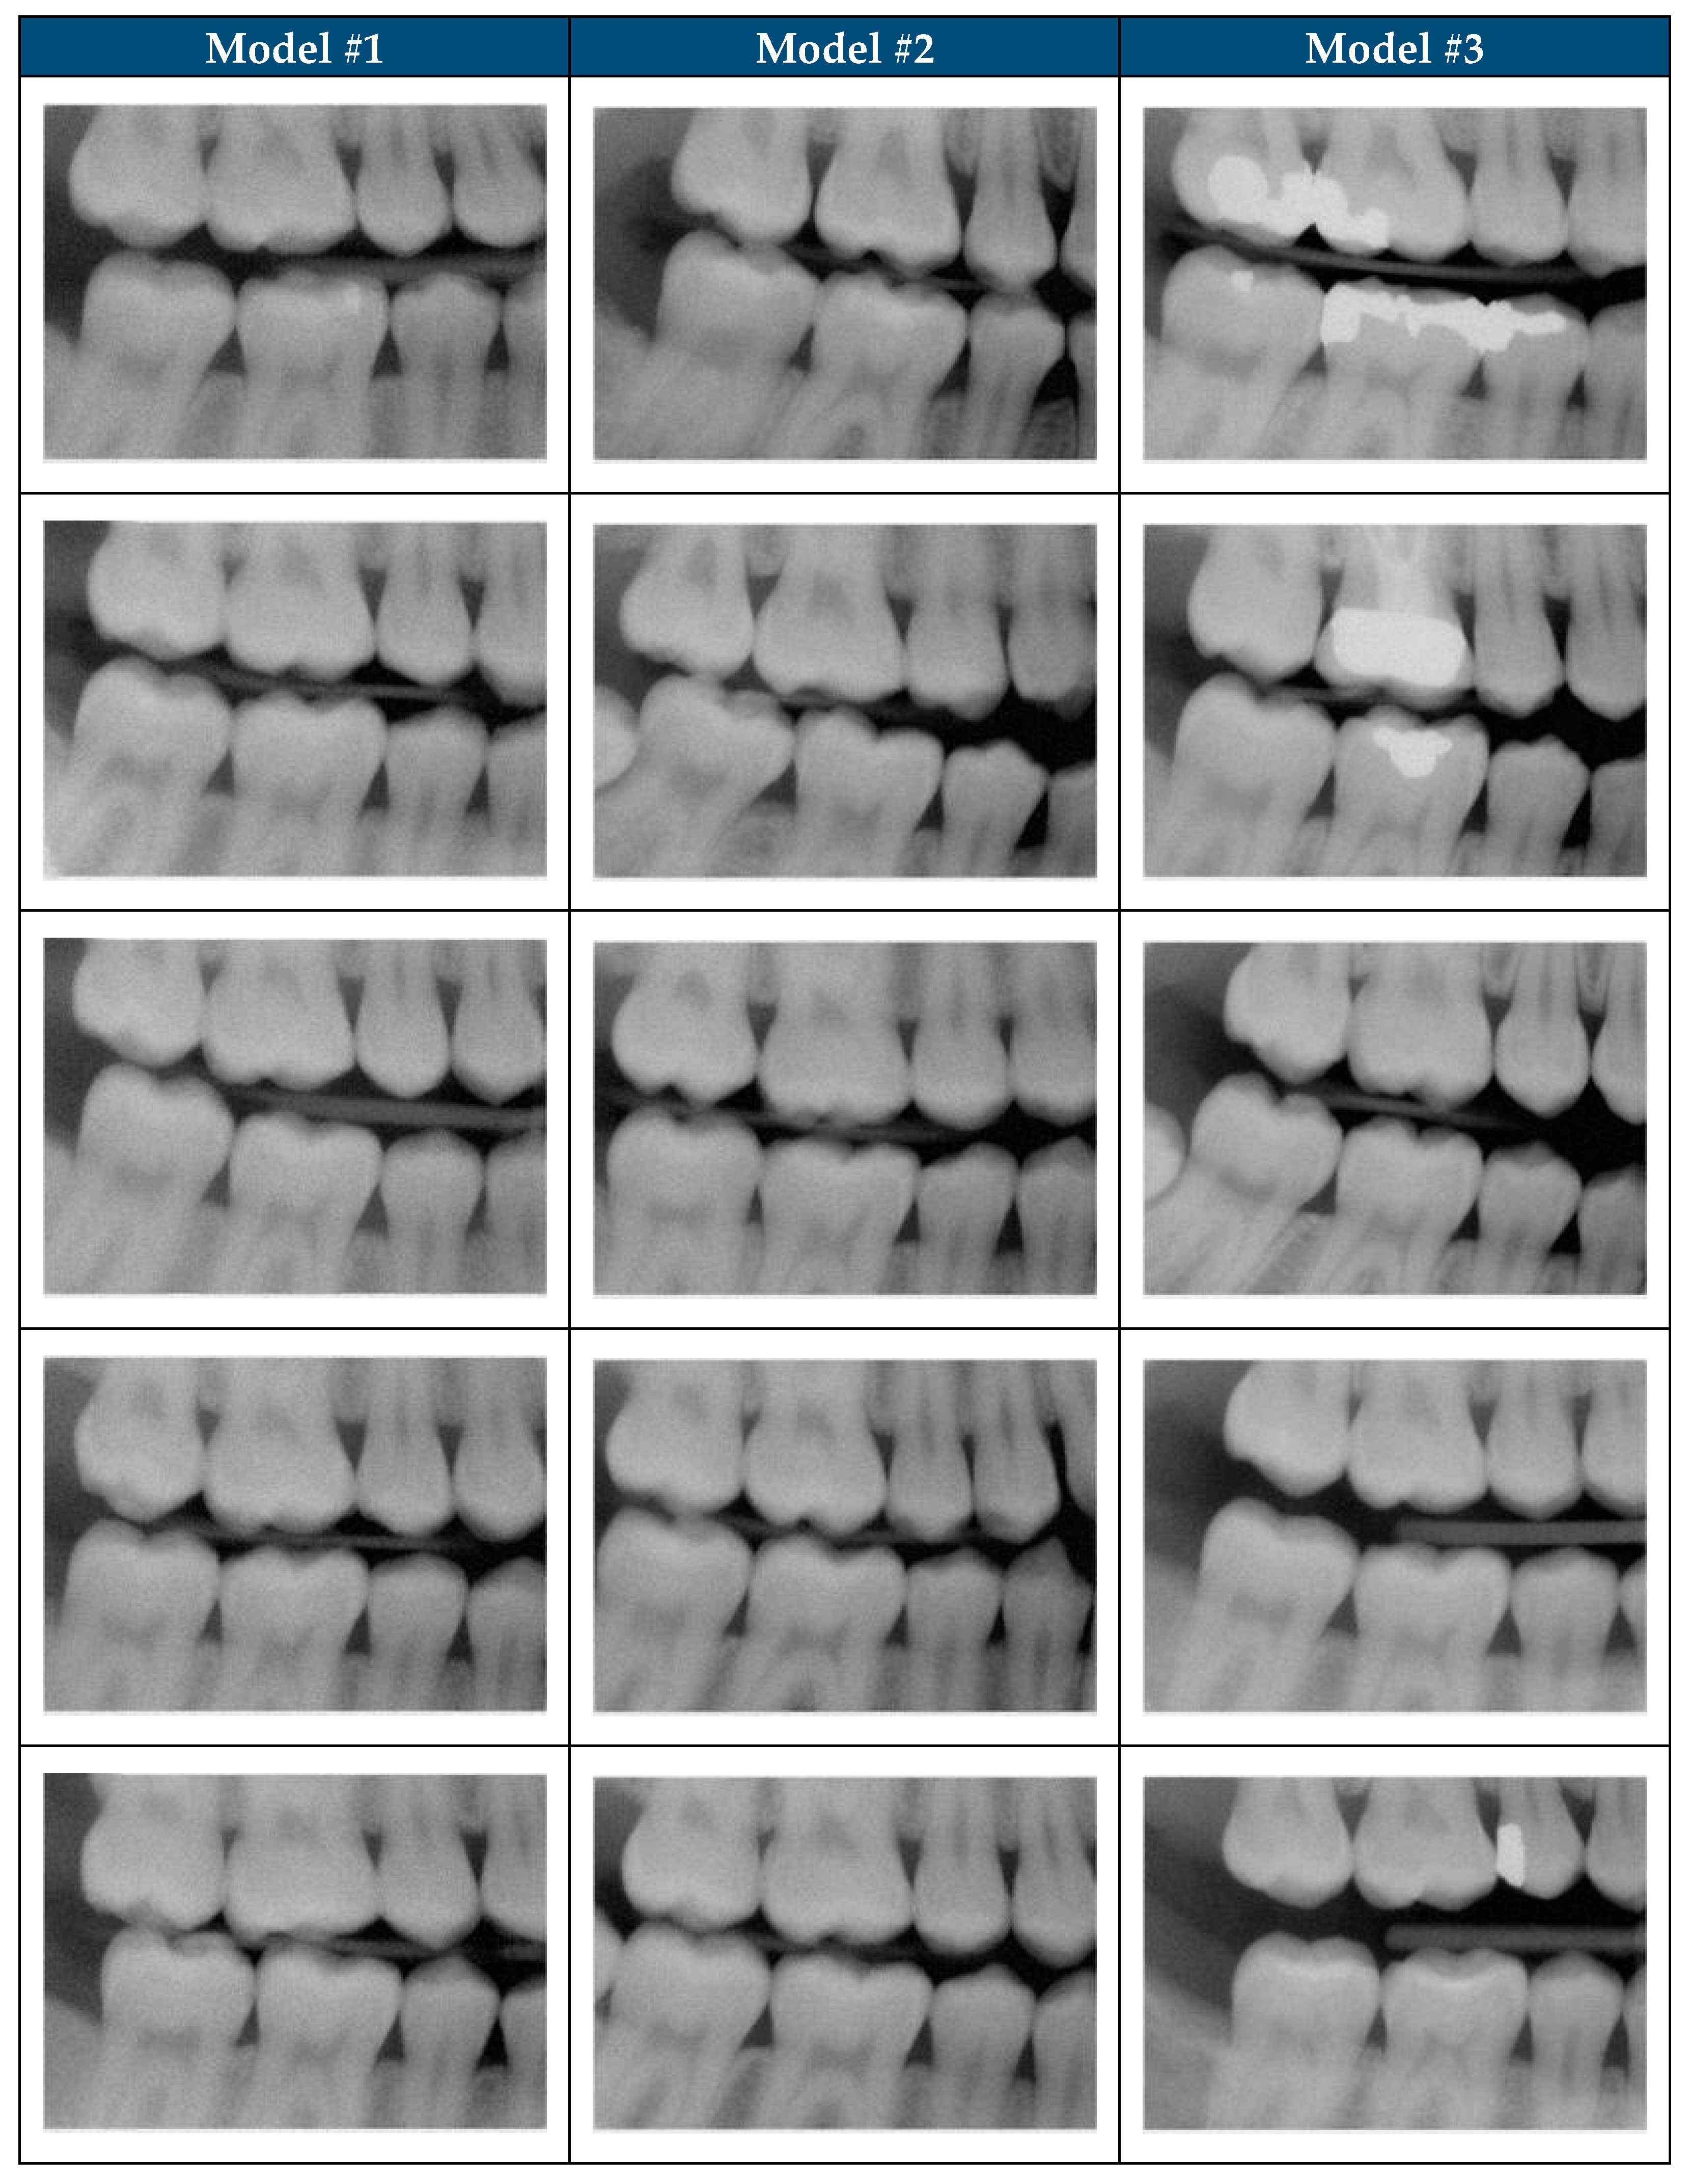

2.5.3. SDR Model #1

2.5.4. SDR Model #2

2.5.5. SDR Model #3

3.3. Objective Analysis of Model Performance